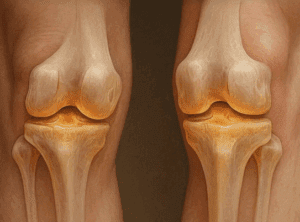

Kolagen jest jednym z najważniejszych białek organizmu. Stanowi podstawę strukturalną tkanek łącznych, takich jak chrząstka, ścięgna, kości i skóra. Dla zdrowia stawów kolagen zapewnia elastyczność, wspomaga ruchomość i przyczynia się do utrzymania integralności stawów.

Jednak wraz z wiekiem lub jeśli w naszej diecie brakuje niezbędnych składników odżywczych, naturalna produkcja kolagenu zaczyna spadać. Ten spadek może prowadzić do sztywności stawów, bólu, a w końcu do poważniejszych schorzeń, takich jak zapalenie stawów.